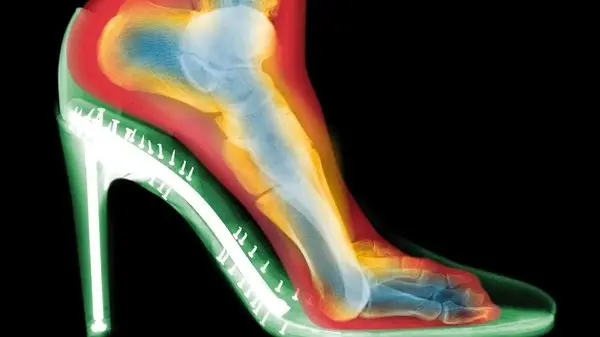

به گزارش رکنا،استفاده مداوم از کفش‌های پاشنه‌بلند ممکن است به تغییر دائمی فرم پاها، ایجاد قوز شست و بروز آرتروز منجر شود. یک متخصص ارتوپدی که پیش‌تر این فرضیه را رد می‌کرد، اکنون با مشاهده اسکن‌های سه‌بعدی پاها هشدار جدی می‌دهد.

گلدبرگ با انجام دو اسکن از پای یک شخص، یکی بدون کفش و دیگری با کفش پاشنه‌بلند، به نتایج شگفت‌انگیزی رسید:

فشردگی انگشتان: انگشتان پا در داخل کفش‌ها به شدت به هم فشرده شده بودند.

انحراف شست پا (بونیون): مفصل شست پا به سمت خارج منحرف شده بود.

انگشتان چنگالی: انگشتان کوچک‌تر برای کنترل تعادل، در حالت قفل‌شده و خمیده قرار گرفته بودند.